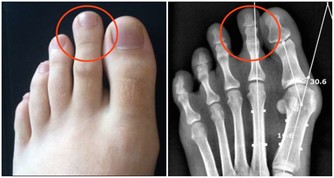

這種放屁可能是癌症的徵兆:

消化專家進一步提醒,當屁噴糞便或粘液時,有可能是直腸有炎症或腫瘤,不容忽視。